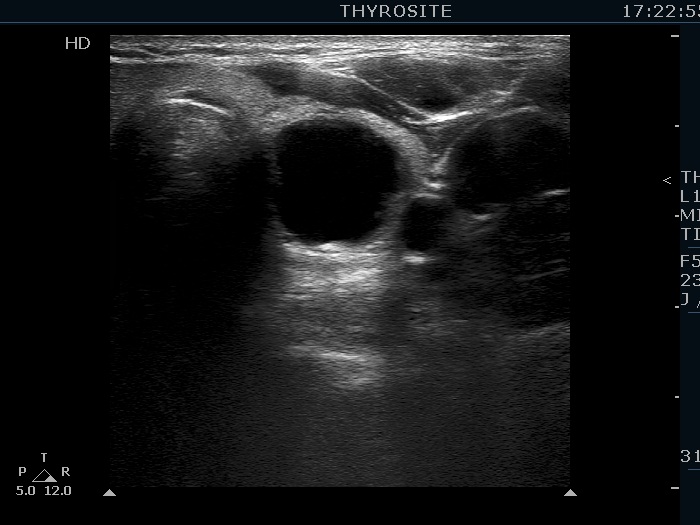

Ultrasonography. The thyroid was echonormal. There were several hypoechogenic lesions in the right lobe. The left lobe had an upper, solid and a lower cystic nodule. The former had both echonormal and moderately hypoechogenic parts and presented halo sign. The cystic nodule had a very tiny solid area in the dorsal part. Nonetheless, before aspiration it was unclear whether this would be a pure cyst or not. After aspirating 2 mL serous fluid a large, moderately hypoechogenic solid area replaced the previous cystic field and it became evident that this is in fact a central type cystic nodule.